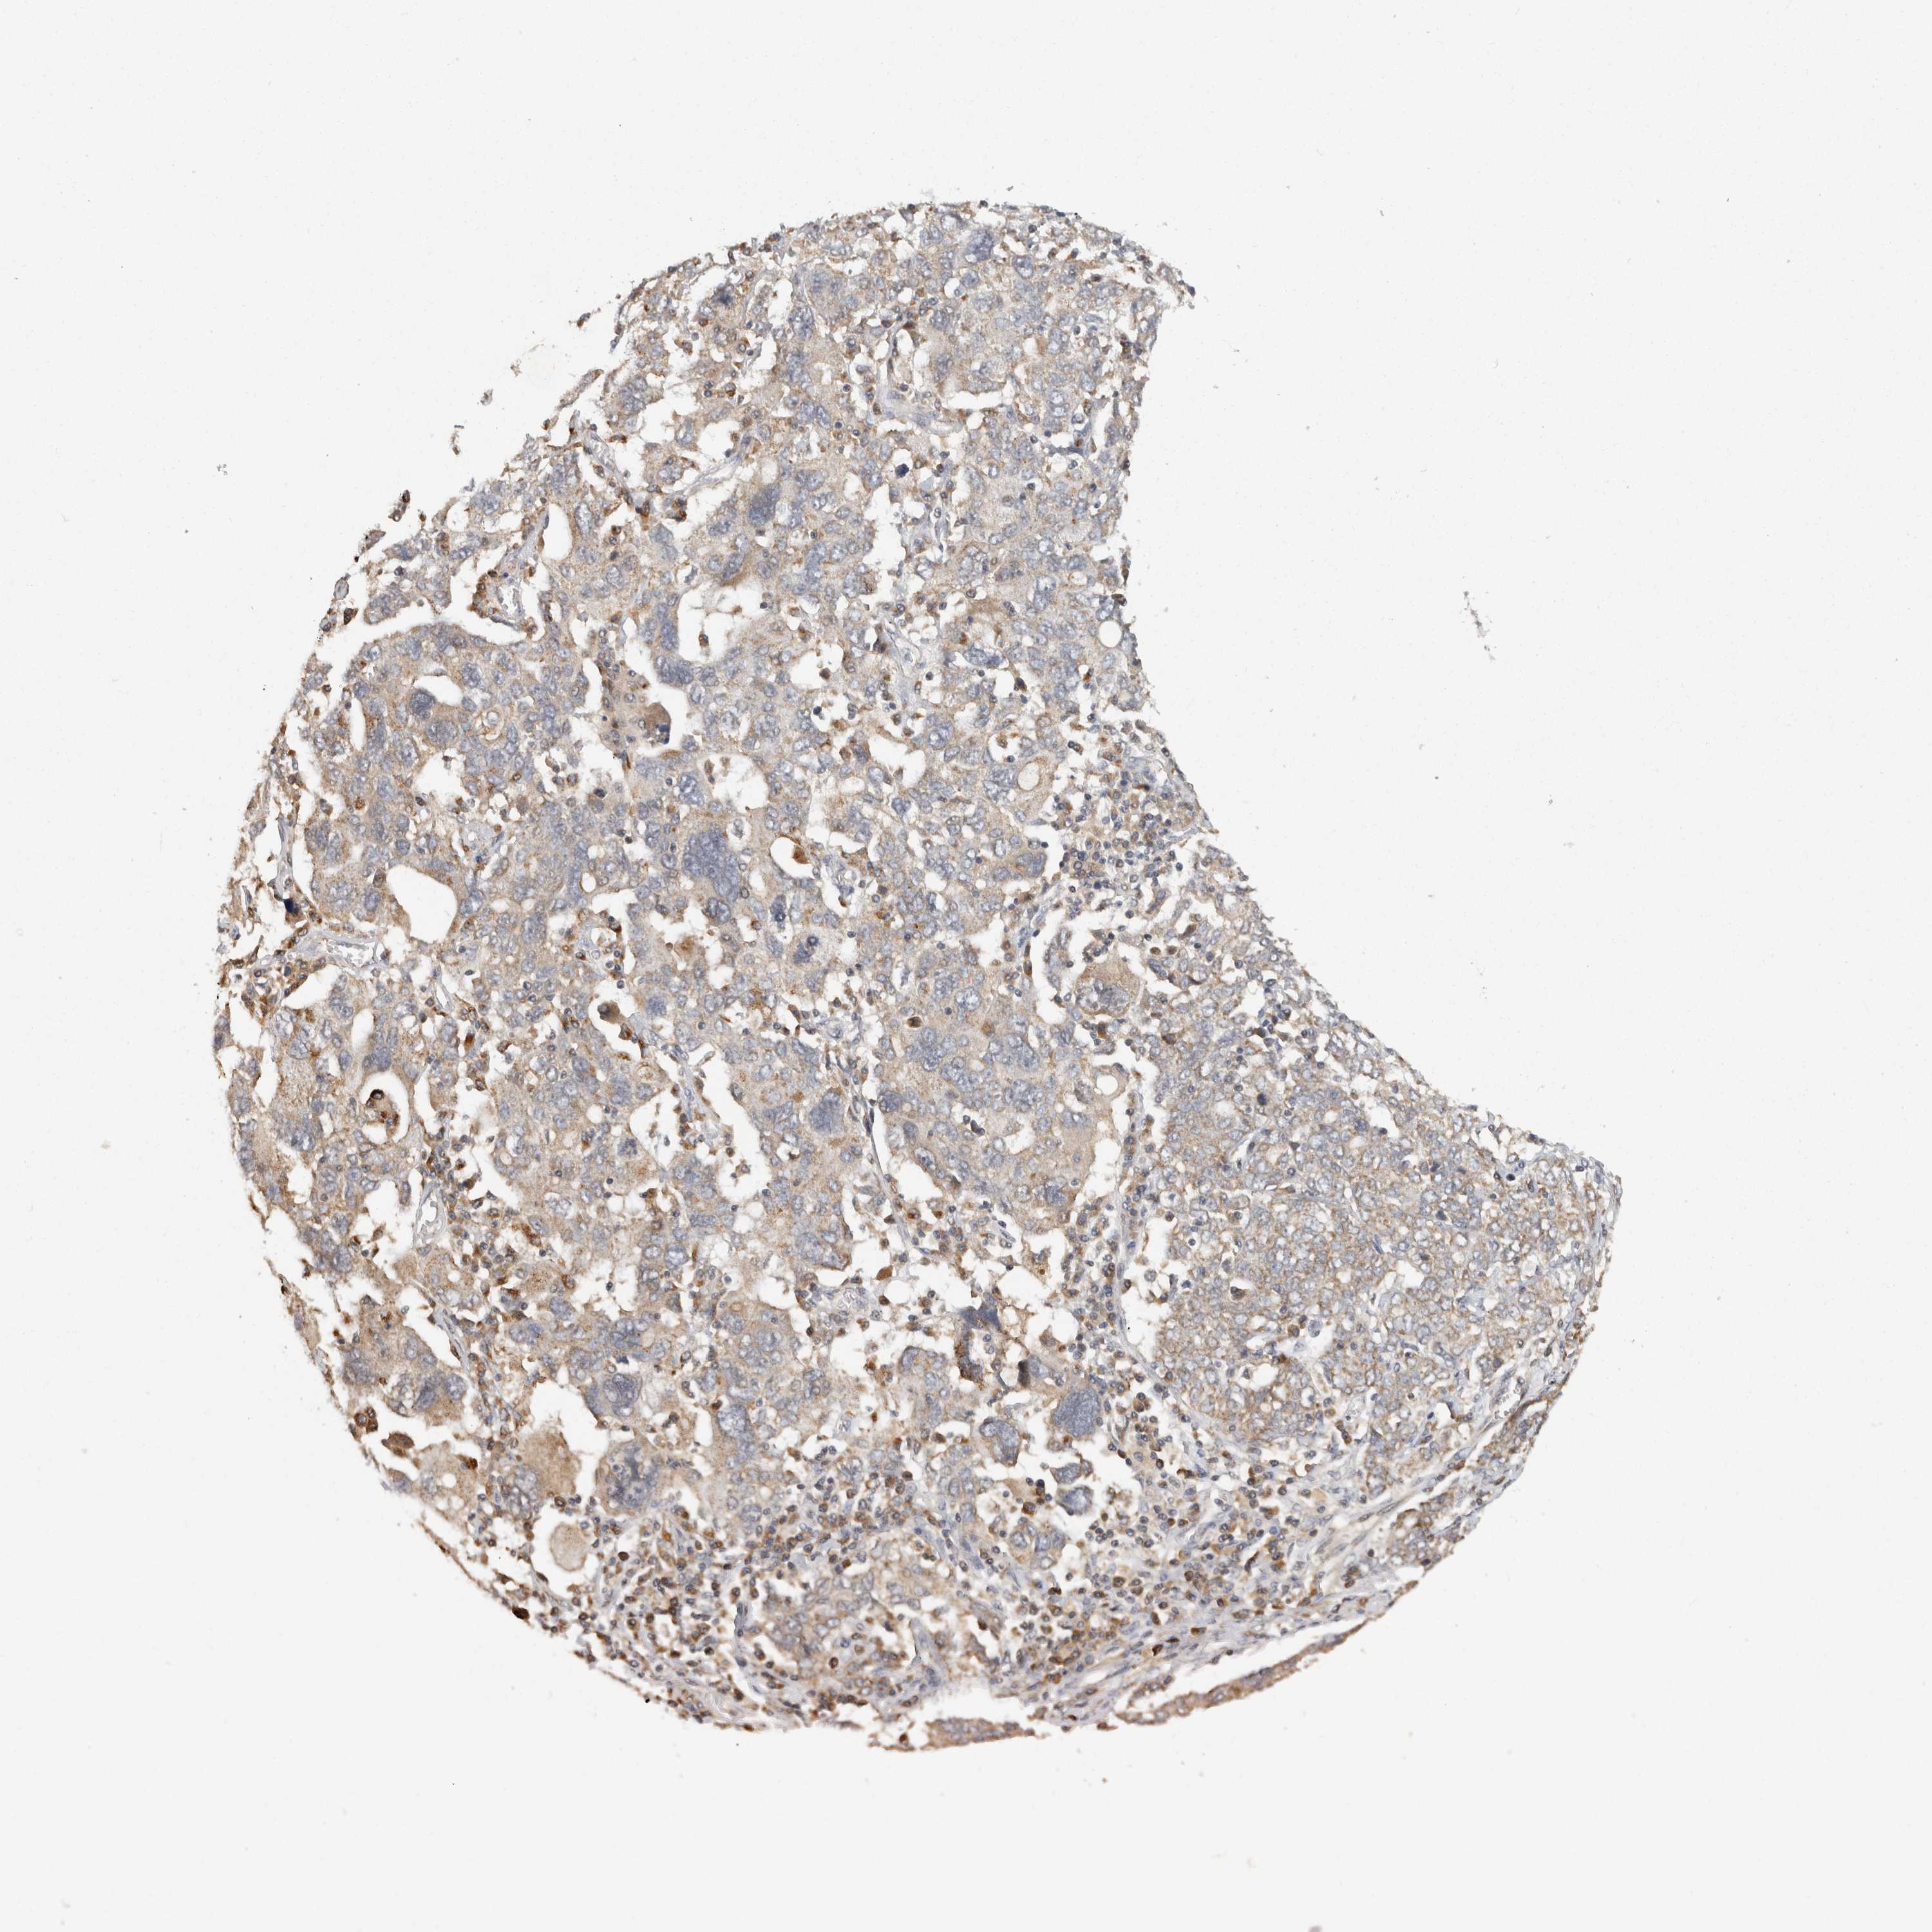

OVARIAN CANCER - Protein expressioni

A mouse-over function shows sample information and annotation data. Click on an image to view it in a full screen mode. Samples can be filtered based on level of antibody staining by selecting one or several of the following categories: high, medium, low and not detected. The assay and annotation is described here.

Note that samples used for immunohistochemistry by the Human Protein Atlas do not correspond to samples in the TCGA dataset.

Antibody stainingi

Antibody staining in the annotated cell types in the current human tissue is reported as not detected, low, medium, or high, based on conventional immunohistochemistry profiling in selected tissues. This score is based on the combination of the staining intensity and fraction of stained cells.

Each image is clickable and will lead to virtual microscopy that enables deeper exploration of all samples and also displays staining intensity scores, fraction scores and subcellular localization as well as patient and tissue information for each sample.

Antibody HPA025811

Cystadenocarcinoma, serous, NOS

Carcinoma, endometroid

Cystadenocarcinoma, mucinous, NOS

Carcinoma, NOS